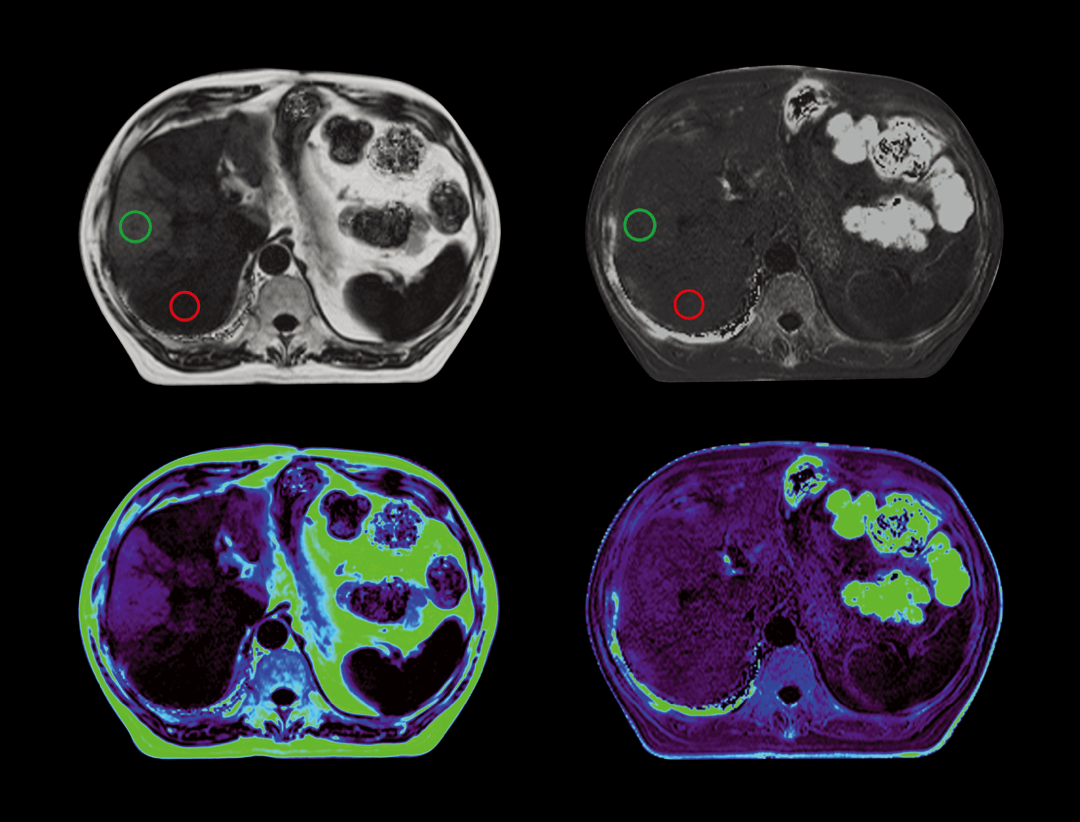

脂肪定量

无创检测组织内脂肪含量及铁沉积,一次扫描输出多参数图像,可以同时提供精确脂肪含量值以及铁沉积程度。